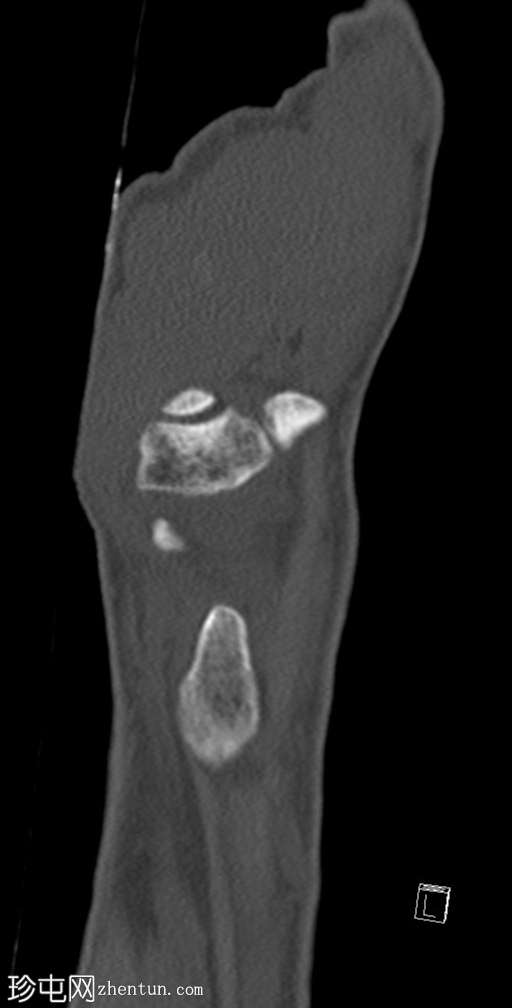

CT轴位、矢状位和冠状位片显示三角骨背侧粉碎性撕脱性骨折。

未见其他骨折。